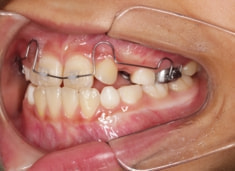

治療開始時

検査時のレントゲン分析では、上下顎の関係は、上顎の劣成長があり下顎前突傾向という値がでておりましたが、前歯ジャンプ後はフェイスマスクの効果もあり、上下顎の関係は正常化しています。

上顎が若干優位になっていますので、今後の下顎の成長のための貯金になっているくらいです。